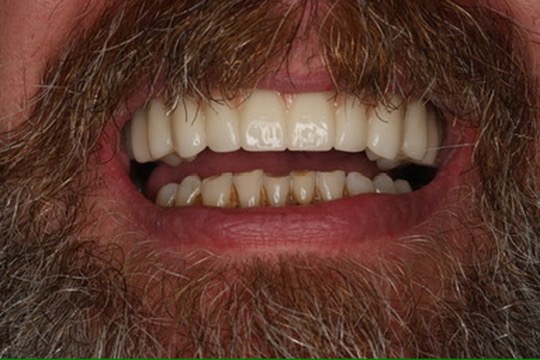

Cases finished, under one roof.

West Market Family Dental Care, Pottsville. Photographs unedited.

Tooth-coloured composite fillings — biomimetic restorative.